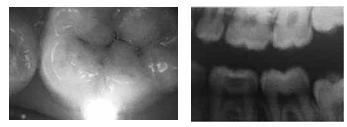

Com base nas figuras acima, que mostram os aspectos clínico e radiográfico do exame dentário do arco inferior esquerdo, assinale a opção correta.